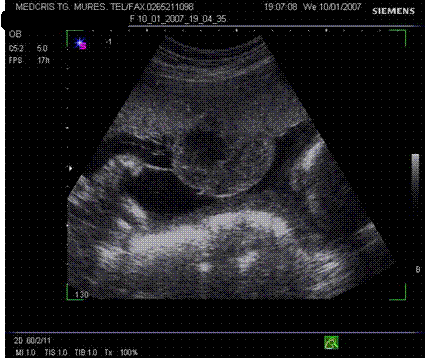

Fig. nr.217. Placenta praevia centrala la 15 saptamani ( linia indica raportul placenta praevia cu orificiul cervical intern)